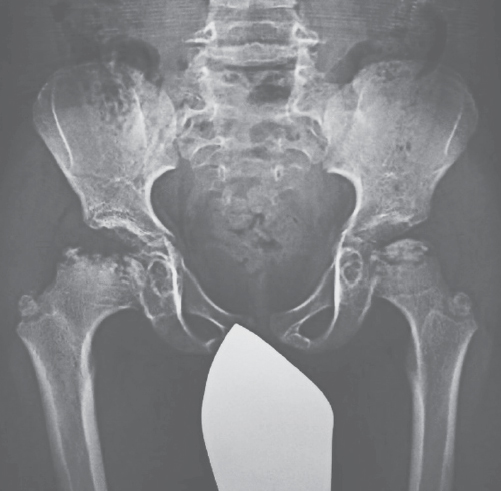

- Бучинская Н.В., Костик М.М., Чикова И.А., и др. Скелетные проявления при мукополисахаридозах различных типов//Гений ортопедии. – 2014. – № 2. – C. 81–90. [Buchinskaya NV, Kostik MM, Chikova IA, et al. Skeletal manifestations for mucopolysaccharidoses of different types. Orthopaedic Genius. 2014;(2):81-90. (In Russ.)]